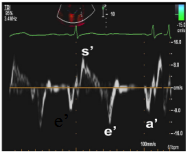

10、二尖瓣环运动速度指标

左室舒张功能受损

①室间隔侧e’< 7 cm/s;

②侧壁侧e’< 10 cm/s;

③平均E/e’> 14